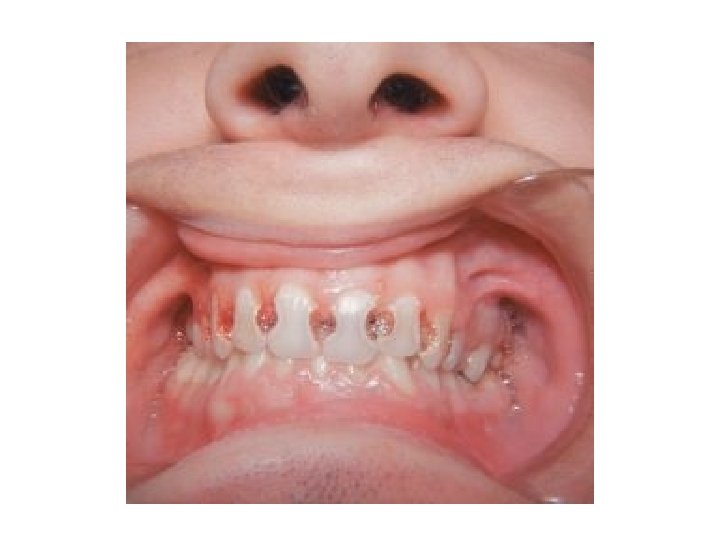

ACUTE DENTAL CARIES - Rapid clinical course & early pulp involvement - Process rapid little time for deposition of sec. dentin. Dentin stained a light yellow - Rampant caries, affecting deciduous dentition nursing bottle caries - Commonly 4 maxillary incisors followed by first molar and then cuspids - Absence of caries in mandibular incisors distinguished from ordinary rampant caries